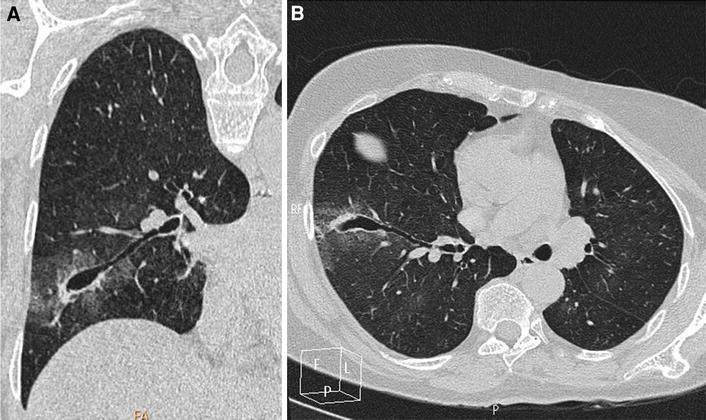

A 68-yr-old-man had general anesthesia for radiofrequency ablation of a single lung metastasis of rectal cancer. The thoracic computed tomography scan with the patient in the prone position after tracheal intubation and before performing radiofrequency shows an acquired bronchial ectasia (10 mm in diameter) of the right subsegmental B6 bronchus and associated ground-glass opacity due to local hemorrhage in the B6 segment

In the second case, a 4-mm diameter bougie injured a 2.1-mm diameter subsegmental bronchus. Radiofrequency ablation of the single lung metastasis was performed successfully without any complication. The patient presented a slight hemoptysis on day one and was discharged after hospitalization for 48 hr. A CT scan one month later showed a complete resolution of the bronchial injury.